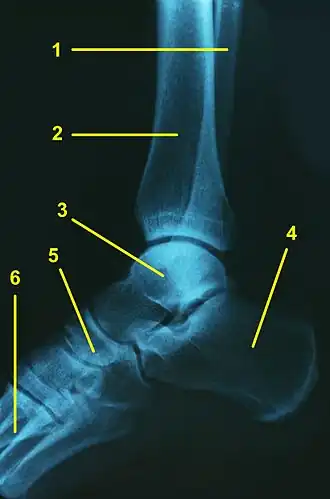

L'articulation talo-crurale (ou articulation tibio-astragalienne ou articulation tibio-tarsienne ou articulation du cou-de-pied ou articulation de la cheville) est l'articulation trochléenne qui unit le pied à la jambe au niveau de la cheville.

L'articulation talo-crurale est formée par les extrémités distales du tibia et de la fibula formant un ensemble tenon - mortaise avec le talus. Les deux os de la jambe forment ensemble une mortaise qui enserre le tenon formé par le talus.

L'articulation talo-crurale met en jeu :

- la facette articulaire de la malléole médiale,

- la surface articulaire inférieure du tibia,

- la facette articulaire de la malléole latérale.

Ces trois facettes formant la pince de la mortaise.

La surface articulaire au niveau du tenon étant formée par la trochlée du talus.